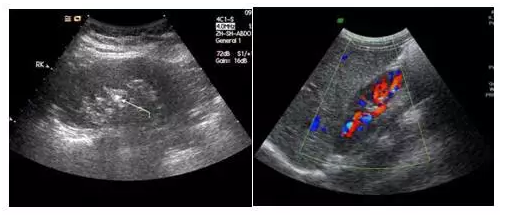

黑白超、彩超該如何選擇

黑白超是聲像圖、彩超是二維圖首先,黑白超和彩超并不是在影像的顏色上有區(qū)別,許多人認為彩超和黑白超的區(qū)別就是彩色電視機和黑白電視機的區(qū)…

黑白超和彩超有什么區(qū)別

黑白超與彩超有何不同

彩超,便攜式和臺式黑白超的不同:一:一個是聲像圖、一個是二維圖黑白超和彩超并不是在影像的顏色上有區(qū)別,其實彩超的“彩”與彩色照片的“…